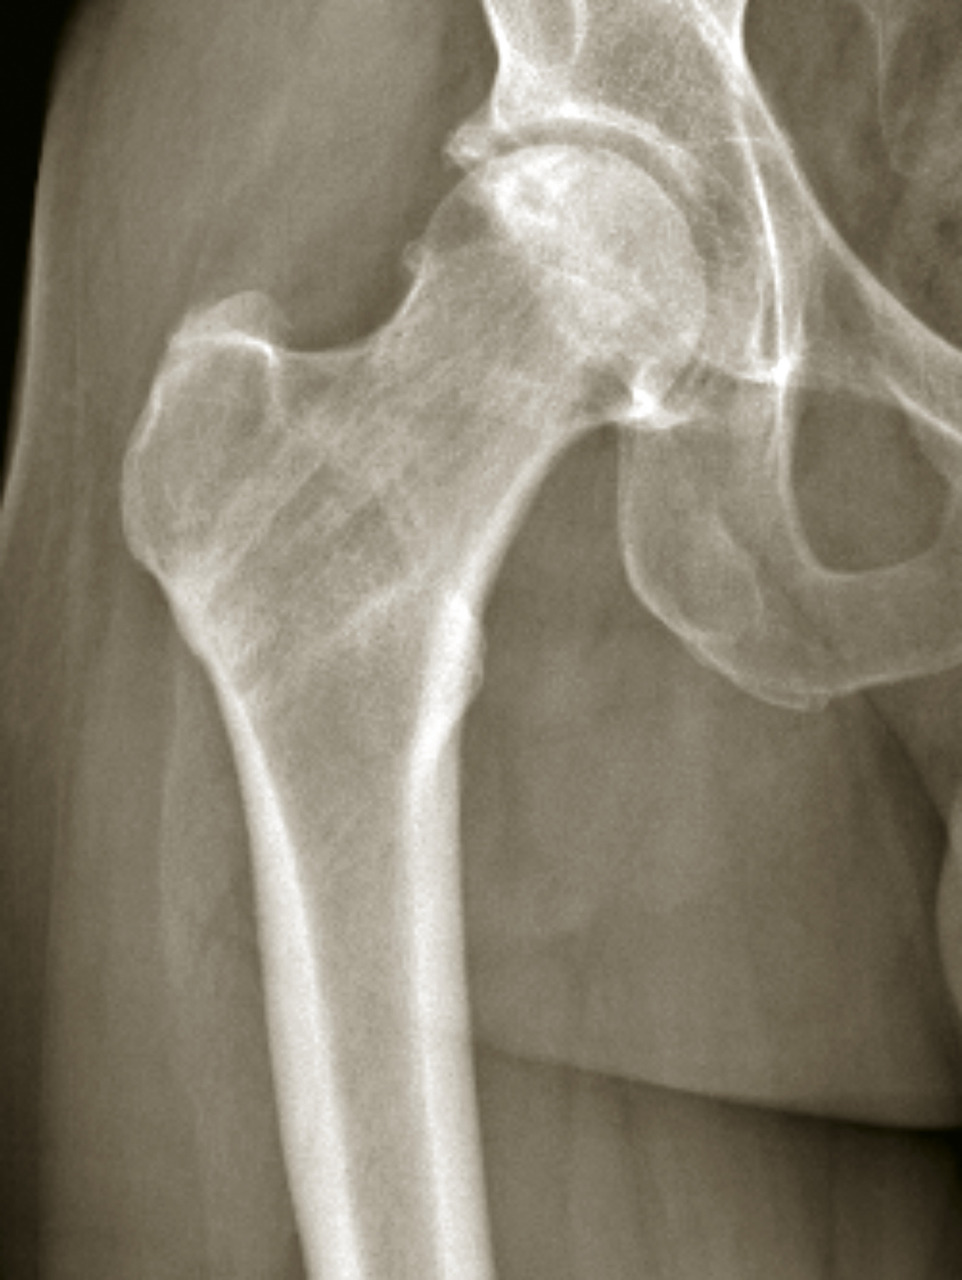

L’extrémité supérieure du fémur se compose de trois régions bien distinctes (fig. 1) : la tête fémorale représentant à peu près deux tiers de sphère est recouverte de cartilage ; le col fémoral assurant la jonction entre la tête et le massif trochantérien ; le massif trochantérien entre la ligne intertrochantérienne et la zone située jusqu’à 2,5 cm sous le petit trochanter. La tête et le col fémoral sont intracapsulaires. Le col est composé d’un os cortical. Il est soumis à des contraintes en cisaillement auxquelles un système de travées osseuses ogival lui permet de résister (fig. 2). Le massif trochantérien est formé d’un os beaucoup plus spongieux et bien vascularisé. La tête fémorale est essentiellement vascularisée par l’artère circonflexe médiale (fig. 3) qui aborde le col fémoral le long de la ligne intertrochantérienne, court le long du col à sa partie supérieure et donne ses branches terminales à la tête fémorale. Ainsi, toute fracture déplacée du col risque de léser la vascularisation céphalique et d’entraîner une ostéonécrose. En effet, la vascularisation assurée par l’artère du ligament rond et les quelques vaisseaux venant de l'artère circonflexe latérale ne suffisent pas à suppléer cette absence de vascularisation. Ce système vasculaire n’est pas altéré dans les fractures du massif trochantérien.

Les fractures du col du fémur peuvent être classées en fonction de leur siège, sous-capital, basicervical ou transcervical (fig. 6). L’intérêt de cette classification est que les fractures basicervicales sont des fractures qui préservent souvent la vascularisation de la tête et qui peuvent donc être traitées par ostéosynthèse. Elles peuvent être classées en fonction de l’orientation du trait de fracture. C’est la classification de Pauwels (fig. 7). Toutefois, la classification la plus utilisée est la classification de Garden (fig. 8). Son intérêt réside dans le fait que plus le grade est élevé et plus le risque d’ostéonécrose de la tête fémorale est important. Il s’agit d’une classification fondée sur l’analyse des travées osseuses du col fémoral sur un cliché radiographique de face :

• le type I est une fracture avec impaction du col responsable d’une fracture engrenée, déplacée en valgus avec verticalisation des travées de compression. Elle est en général assez stable du fait de l’engrènement, et le risque de lésion vasculaire est faible ;

• le type II est une fracture non déplacée sans aucune modification des travées osseuses. Malgré l’absence de déplacement, le risque de nécrose est de l’ordre de 20 %, et est peut-être en rapport avec l’hématome fracturaire responsable d’une tension intracapsulaire ;

• le type III est une fracture déplacée en varus avec conservation d’une charnière à la face inférieure du col. Le risque de lésion vasculaire est important, avec une nécrose dans 50 % des cas ;

• le type IV est une fracture déplacée avec perte de contact des fragments, notamment au niveau de la charnière, augmentant encore le risque de nécrose au-delà de 50 %. Son aspect radiographique est souvent éloigné des schémas car, du fait de la désolidarisation complète entre le fémur et la partie proximale de la tête et du col, il se produit une rotation externe complète du fragment distal (fig. 9), comme en témoigne le déroulement du petit trochanter particulièrement visible dans ce cas-là.

L’inconvénient de cette classification est de ne pas tenir compte de l’aspect sur le profil où la bascule postérieure de la tête peut être importante, notamment dans les fractures Garden I. Le pronostic pour ce type de fracture est alors davantage à l’instabilité, avec un risque de déplacement secondaire, qu’à la nécrose céphalique.